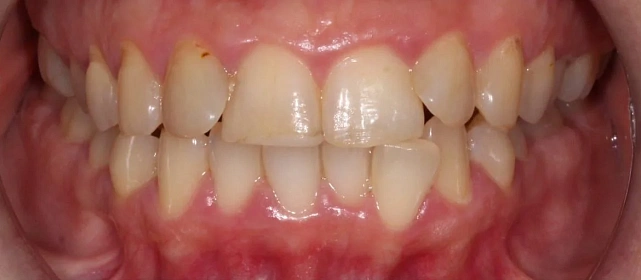

Зубы выровнены, смыкание нормализовано. Установлены несъёмные ретейнеры на обе челюсти, изготовлены ретенционные капы. Пациентка предварительно проконсультирована ортопедом онлайн.

Решение: Поставили элайнеры 3D Smile на обе челюсти. Лечение заняло 4 года и потребовало нескольких последовательных этапов коррекции. Капы менялись каждые 1–2 недели, на контрольных визитах отслеживали прогресс и выдавали новые наборы. Зубы встали в правильное положение, смыкание нормализовалось. Зафиксировали ретейнеры на обе челюсти, изготовили ретенционные капы. Пациентка прошла онлайн-консультацию с ортопедом для оценки дальнейших шагов.

Лечение потребовало нескольких последовательных этапов — каждый дозаказ кап уточнял положение зубов, которые не полностью отреагировали на предыдущий курс. Элайнеры 3D Smile позволяют работать поэтапно, корректируя план по ходу. Результат получен, ретейнеры зафиксированы. Рекомендовала пациентке консультацию ортопеда для оценки состояния зубов после лечения